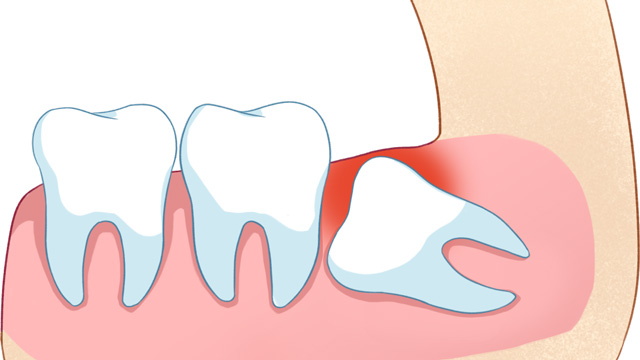

01智齿挤压邻牙,导致牙齿拥挤/移位

这是最常见的拔除原因。正畸的核心需求之一一般是“排齐拥挤牙齿”,而智齿作为口腔中最后萌出的牙齿(通常在20岁左右萌出),由于生长位置特殊、空间有限,很可能会持续挤压旁边的第二磨牙,导致第二磨牙倾斜、移位,进而引发整个牙列拥挤。

如果不拔除这颗“肇事智齿”,即使通过正畸排齐了牙齿,后期也会因为智齿的持续挤压,导致牙齿再次拥挤、反弹。

有些智齿虽然目前没有疼痛、没有挤压邻牙,但拍X光片后发现,它属于“埋伏阻生”(完全埋在牙龈下),或者生长方向异常,未来很可能会萌出、挤压邻牙,甚至引发囊肿、肿瘤等问题。对于这类堪比“定时炸弹”的智齿,医生通常会建议拔除,避免后续出现更严重的口腔问题。

智齿萌出时,牙龈会形成一个“盲袋”,容易堆积食物残渣和细菌,进而引发“智齿冠周炎”——牙龈红肿、疼痛、流脓,严重时还会导致脸颊肿胀、发烧,影响正常饮食和生活。